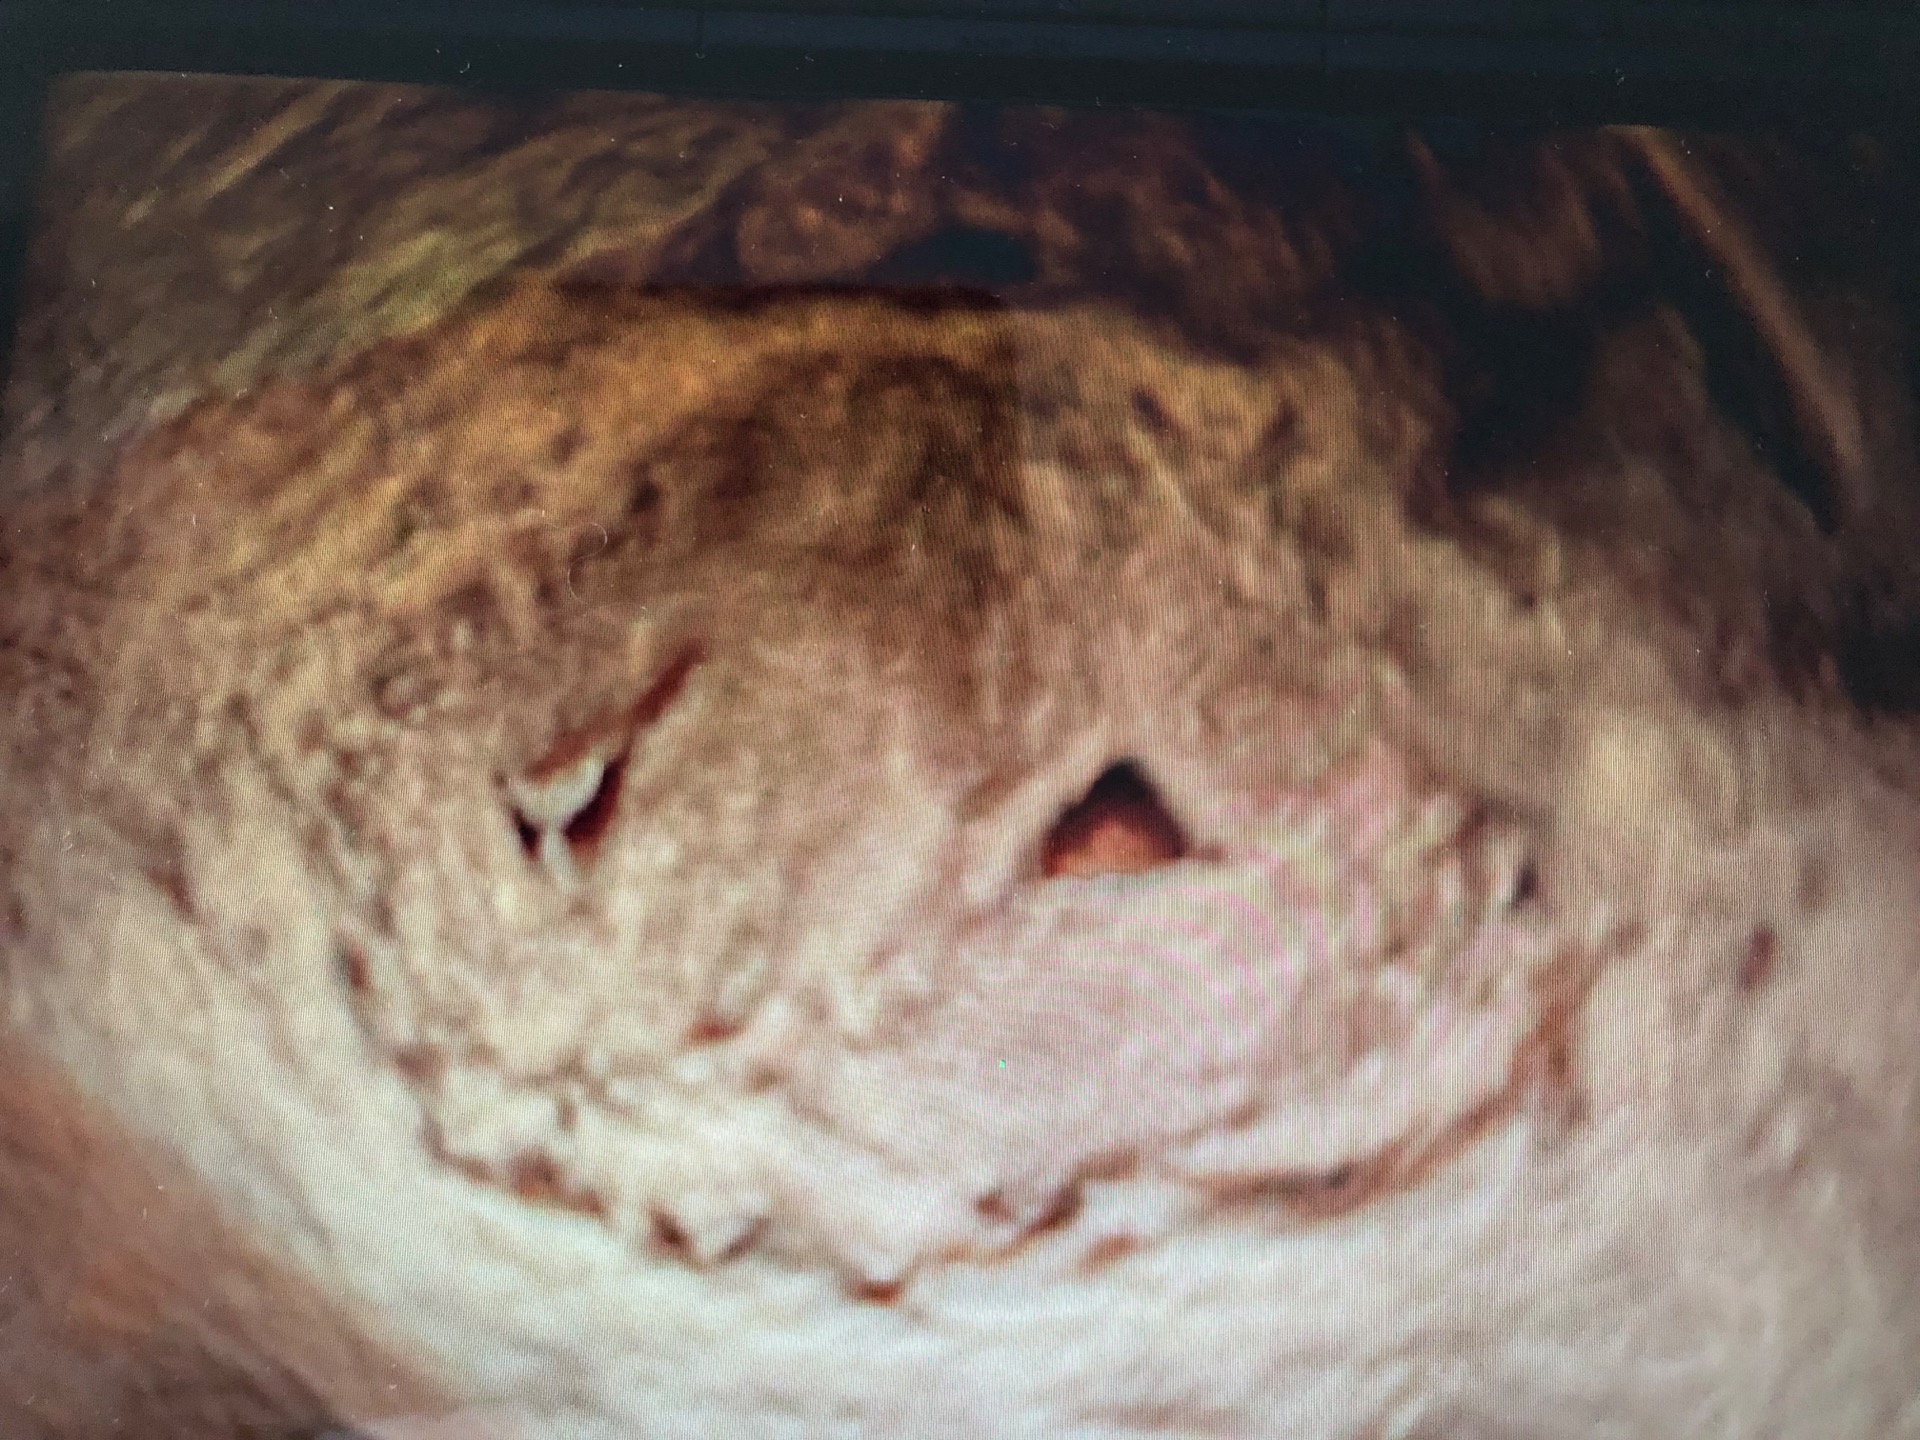

U rizikové skupiny žen, kam řadíme ženy v reprodukčním věku, u kterých předpokládáme na základě gynekologické prohídky nebo subjektivních potíží přítomnost VVV dělohy, je třeba vadu potvrdit 3D vaginálním ultrazvukovým vyšetřením. U žen s pravidelným menstruačním cyklem provádíme vyšetření mezi 17.-25. dnem cyklu (první den cyklu je první den menses). Ke zjištění typu vrozené vývojové vady dělohy se dříve používala kombinace operačních výkonů- laparoskopie a hysteroskopie. Současné 3D ultrazvukové vyšetření je pro pacientku příjemné, nebolestivé a rychlé a operační výkony zcela nahradí.

Autor ultrazvukových obrázků: doc. MUDr. Ivana Kacerovská Musilová, PhD.